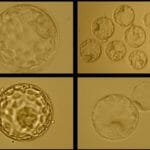

Hatching Blastocyst

Early Hatching Embryo

Hatched Blastocyst

Morula to Blastocyst Embryogenesis

Morphologically Normal Blastocysts